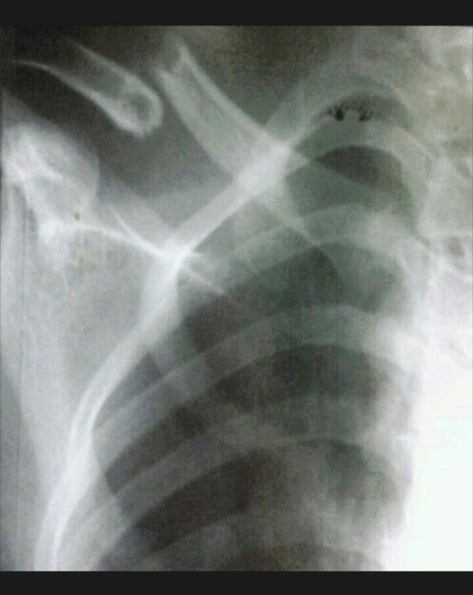

Patah Tulang Kering (Tibial Bone Fracture)

Telepon seluler berdering kencang. Panggilan dari dokter jaga ugd melaporkan pasien baru akibat kecelakaan lalu lintas yang baru saja terjadi. Ibu paruh baya datang dengan luka menganga pada tungkai kiri. Dari gambaran klinis yg dikirimkan tampak daging terburai. Darah merubah warna perlak yang melapisi tempat tidur pasien menjadi merah. Tampak pula dua potongan (fragmen) tulang yang keluar. Berada diluar daging tepatnya

“Dok, dari pengukuran saturasi didapatkan hasil ‘0’ (null) diseluruh jari”. Dokter UGD menjelaskan seluruhnya dengan gamblang dan terinci. “Siapkan operasi cito -istilah untuk tindakan operasi darurat ya”. Seraya segera mengambil kunci motor bergegas menuju rumah sakit.

Keadaan saat awal operasi (durante op) bagian ujung kaki (distal) tampak berwarna pucat kebiruan. Tidak dijumpai perdarahan aktif. Hematom ada diantara jaringan bawah kulit (subkutis), diantara otot yang tercabik-cabik. Dilakukan tindakan meluruskan kembali tulang, re-aligment sekaligus dilakukan debridemen. Posisi tulang yang pecah fragmented dilakukan re-aligment. Selanjutnya dilakukan fiksasi tulang (external fixation). Penutupan jaringan lunak (soft tissue) dilakukan sedapatnya dengan tarikan regang yang sedikit (minimal tension). Diakhir operasi ujung kaki mulai tampak kemerahan kembali.

Patah tulang tibia (tibial fracture) adalah patah tulang panjang yang paling sering dijumpai khususnya pada bagian batang tulang shaft (plateau, shaft dan plafon). Dari mekanismenya dibedakan menjadi 2 jenis yaitu low energy fracture pattern dan high energy fracture pattern.

Dari mekanisme low energy umumnya didapatkan alibat cidera tidak langsung (torsional injury) dengan ciri khas didapatkan patah tulang fibula pada level yang berbeda, sedangkan untuk mekanisme high energy injury umumnya dari benturan langsung yang seringkali berupa patahan dengan bentuk baji (wedge) atau short oblique dengan bagian yang terpecah (kominutif fragment).

Pengobatan patah tulang tibia dapat berupa pengobatan tanpa operasi ataupun dengan operasi. Pengobatan tanpa operasi dilakukan berupa pemasangan gips (casting) dengan indikasi patah tulang tertutup dengan aligmnen baik.

Pengobatan patah tulang tibia dapat pula dilakukan melalui operasi dengan beberapa indikasi berupa posisi tulang yg tidak baik selah dilakukan reposisi tertutup (unacceptable alignment with closed reduction and gips), cidera jaringan lunak luas yang menyulitkan perawatan, patah tulang dengan tipe segmental dan kominutif.

Lima hari kemudian keadaan ibu itu jauh membaik. Wajahnya nampak cukup bugar untuk bisa pulang. Ujung-ujung jari kedua kakinya sama, tidak ada tanda nekrotik sama sekali. Ekternal fiksasi terpasang kokok menopang tulang tibianya yang pecah belum sepekan lalu.